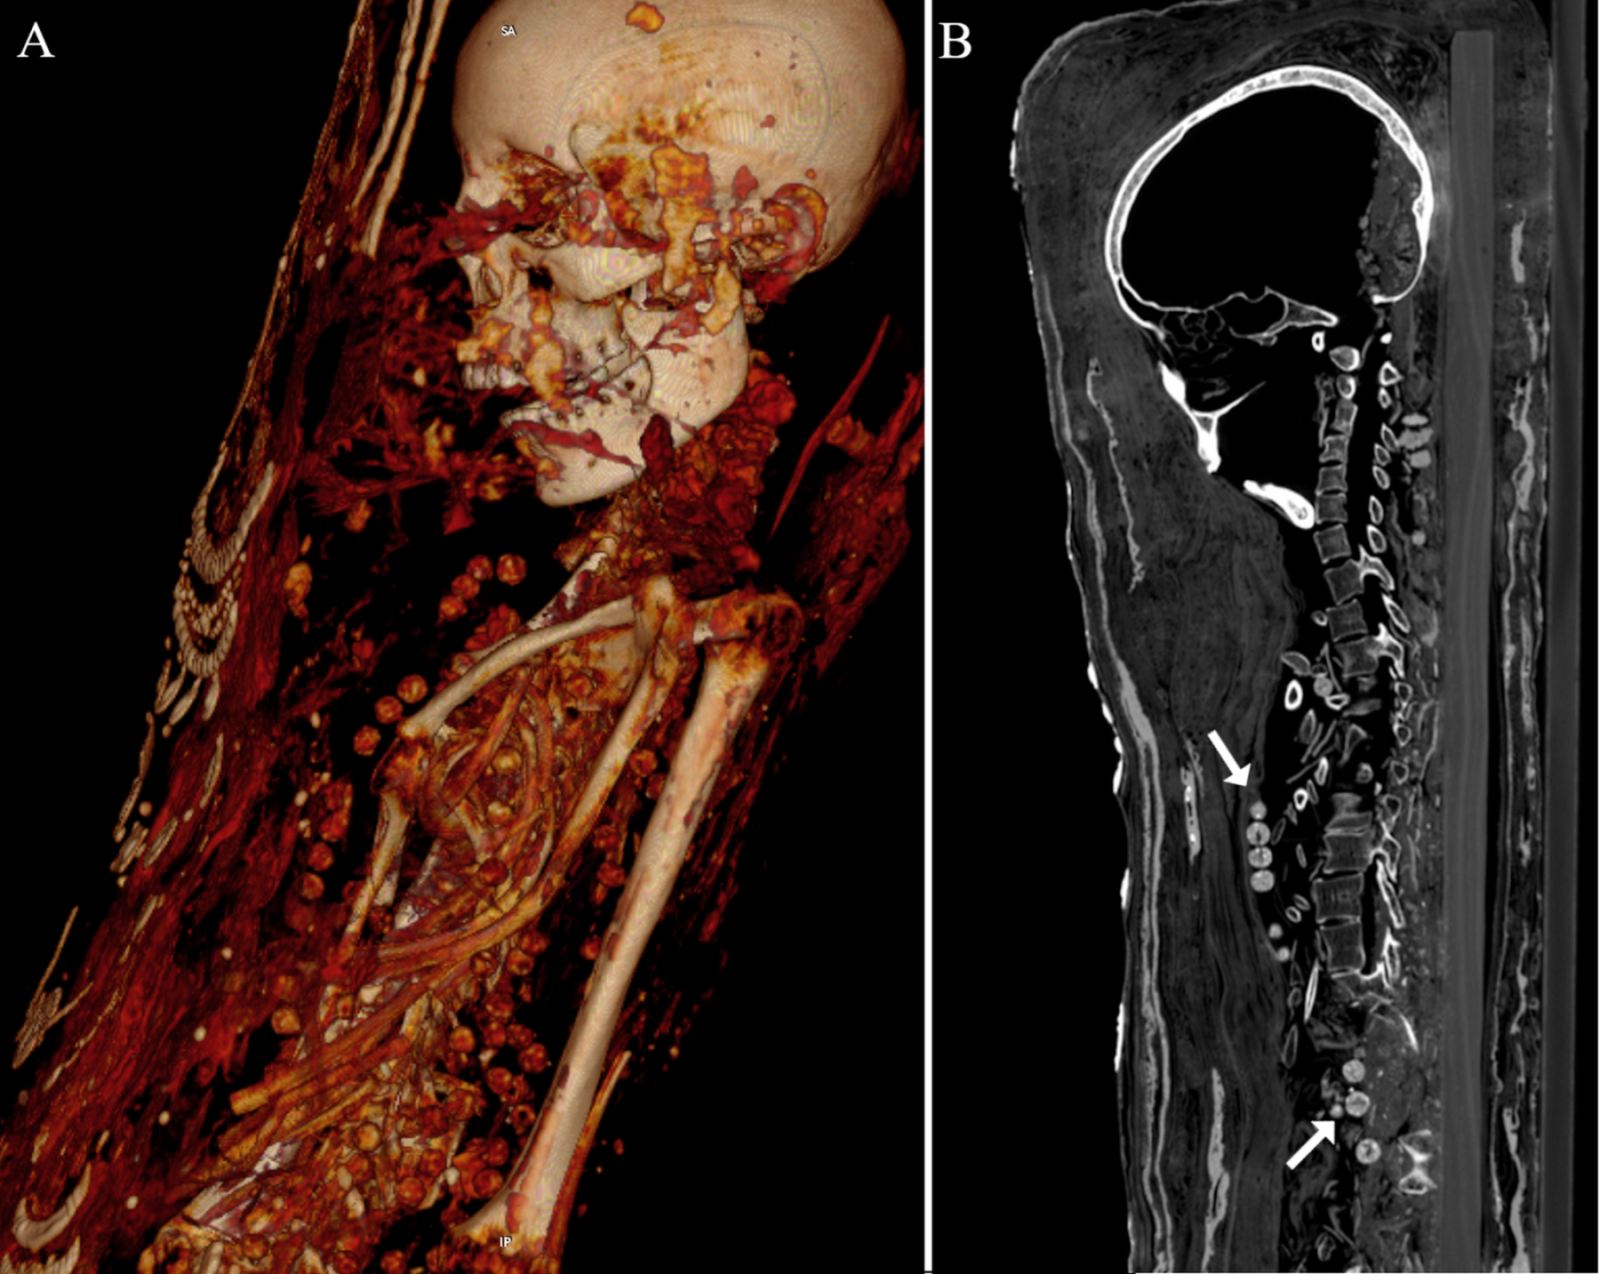

Although Takabuti has been a subject of study since her mummy was first acquired, scanning techniques only recently became advanced enough to determine that the stab wound near her left shoulder was the cause of her death. Retired orthopedic surgeon Dr. Robert Loynes performed the CT analysis. “The CT scan reveals that Takabuti sustained a severe wound to the back of her upper left chest wall,” Loynes said in a statement. “This almost certainly caused her rapid death. However, the CT scan also reveals unusual and rare features of her embalming process.”

For one, Takabuti possessed two rare mutations — an extra tooth, which appears in 0.02 percent of the population, and an extra vertebra, which occurs in 2 percent of the population. Importantly, she also still possessed her heart, which previous research had asserted was missing.